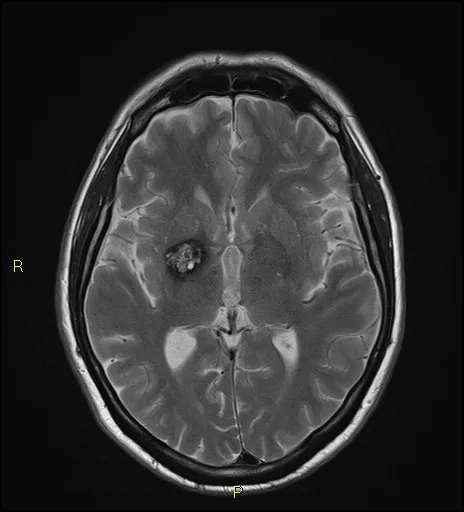

Image of Brain scan showing Cavernoma

Scan image of a cavernoma in the brain

A cavernoma is a cluster of blood vessels that form blood-filled ‘caverns’ in the brain that look like a raspberry. Cavernomas can bleed into the brain and cause a stroke. Cavernomas can also cause a seizure or epilepsy. These symptoms may lead to disability, handicap and occasionally death. About 160 people in the UK each year are diagnosed with a cavernoma that has caused symptoms. In standard practice in the UK, about one fifth of people with cavernomas have ‘active treatment’ with either brain surgery to remove a cavernoma or stereotactic radiosurgery to treat it with radiation.